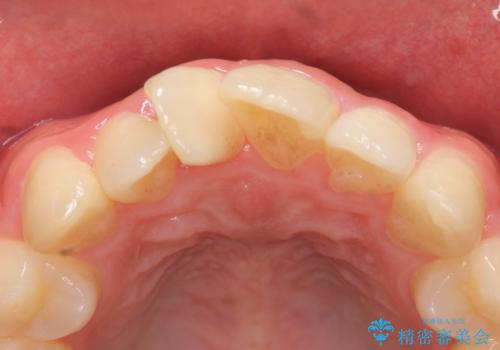

- 上顎前歯の歯並びが気になるが仕事が忙しく矯正治療は難しいため、セラミック矯正で綺麗にしたいといらっしゃった方の症例です。

左右の1番目の歯は傾きが大きいため、セラミッククラウンにするにあたり神経治療を行うことを御了承頂いた上で、前歯4本をオールセラミッククラウン(スペシャル)により補綴しました。